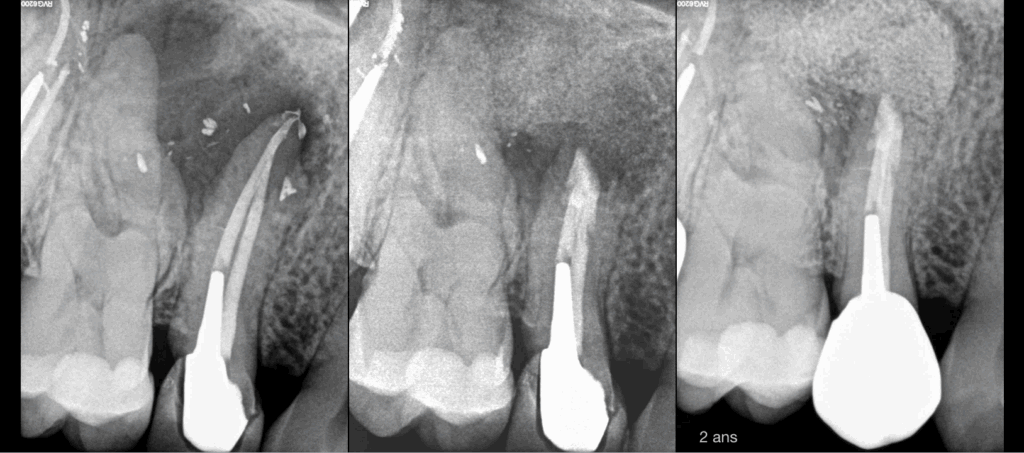

🔍 Une des indications de régénération osseuse guidée en chirurgie endodontique : la lésion apicale de « part en part » (d’une corticale à l’autre).

🦷 𝐏𝐨𝐮𝐫𝐪𝐮𝐨𝐢 ? 𝐀𝐟𝐢𝐧 𝐝𝐞 𝐥𝐮𝐭𝐭𝐞𝐫 𝐜𝐨𝐧𝐭𝐫𝐞 𝐥𝐚 𝐜𝐨𝐦𝐩𝐞́𝐭𝐢𝐭𝐢𝐯𝐢𝐭𝐞́ 𝐜𝐞𝐥𝐥𝐮𝐥𝐚𝐢𝐫𝐞 𝐞𝐧𝐭𝐫𝐞 𝐜𝐢𝐜𝐚𝐭𝐫𝐢𝐬𝐚𝐭𝐢𝐨𝐧 𝐨𝐬𝐬𝐞𝐮𝐬𝐞 𝐞𝐭 𝐜𝐢𝐜𝐚𝐭𝐫𝐢𝐬𝐚𝐭𝐢𝐨𝐧 𝐦𝐮𝐪𝐮𝐞𝐮𝐬𝐞.